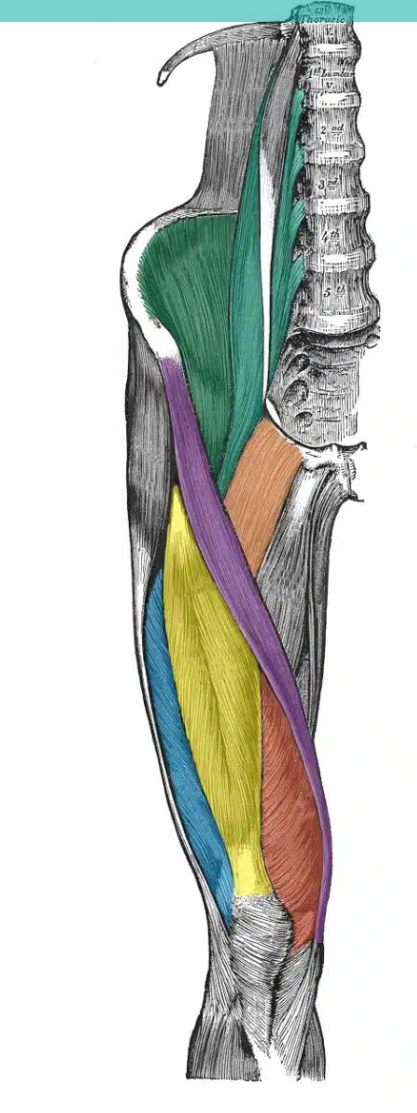

green vertical muscle- close to spine

A

psoas major

How well did you know this?

11

Q

green muscle - in the iliac fossa

12

yellow

rectus femoris

1

Not at all

2

3

4

5

Perfectly

13

red

vastus medialis

14

blue

vastus lateralis

15

purple

sartorius

16

orange

pectineus